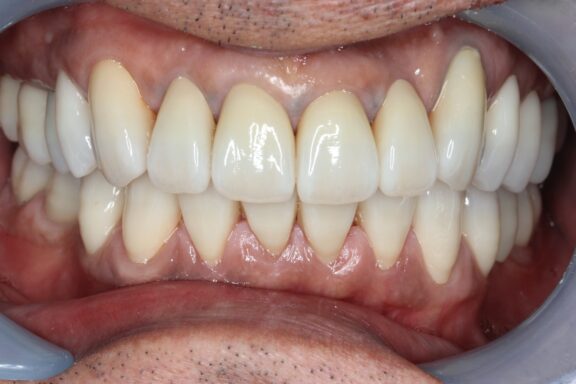

完成がこちらになります。

必要箇所には顕微鏡(マイクロスコープ)にて根管治療を行い、先月、全部の治療が完成しました。

術前、術後で比較すると、とても口腔内が明るくなり、正面から見てもとても若々しく感じます

今回は約1年ほどかけながら順番にゆっくり焦らずしっかりと治療を行っていきました。